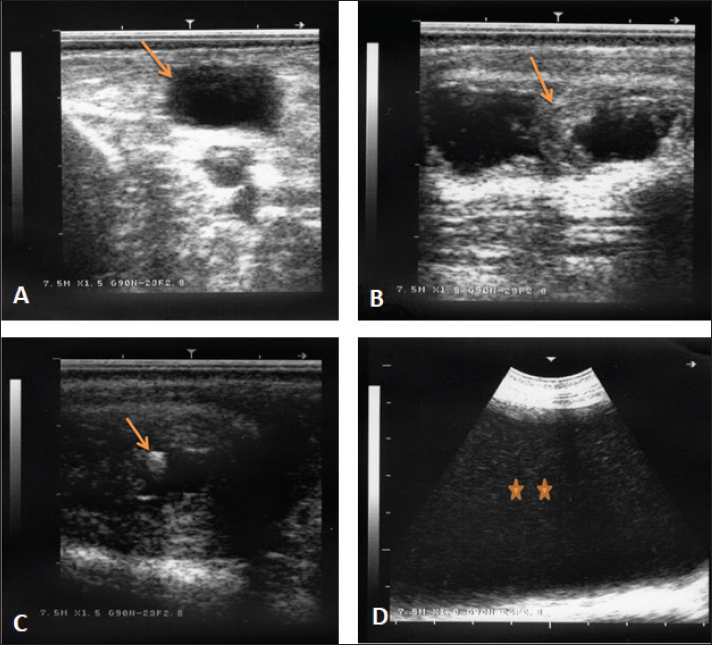

Fig. 6. Ultrasonographic finding in a buck with ruptured bladder due to urethral obstruction by a calculus. Image (A) shows a ruptured and collapsed urinary bladder within the pelvic cavity (arrow). Image (B) shows a dilated urethra with increased wall thickness (arrow). Image (C) shows a calculus within the urethra characterized by acoustic enhancement with distal acoustic shadowing (arrow). Image (D) shows massive abdominal effusions (stars).

Table 1 shows also the sonographic results of the rams and bucks with red urine. These findings included ruptured urinary bladder in 3 (16.7%) (Fig. 6), ruptured urethra in 5 (27.8%) (Figs. 4 and 5), penile calculi in 4 (22.2%) (Fig. 6), uroperitoneum in 6 (33.3%) (Figs. 1 and 6), distended urinary bladder in 7 (38.9%) (Fig. 1), hydronephrosis in 5 (27.8%) (Fig. 2), echogenic deposits in the bladder in 3 (16.7%) (Fig. 3), and ventral urine accumulation in 4 (22.2%) animals (Fig. 5). Laboratory evaluation of a Geimsa-stained blood smear confirmed the infection with B. ovis in three bucks and a ram (Fig. 7). Hemolytic anemia was marked in two bucks and a ram due to chronic copper toxicity (Fig. 8).